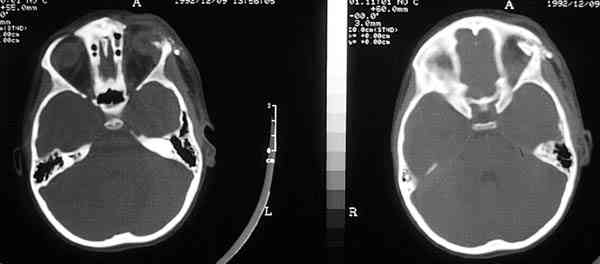

51-18.jpg (9182 bytes)

Figura 18. La contusión frontal produce una neuropatía óptica traumática con pérdida irreversible de visión pese a tratamiento con megadosis de corticoides o descompresión del canal óptico orbitario por la unidad craneofacial. Llamamos la atención de esta patología en golpes inocuos sobre el reborde orbitario superior.

Las pérdidas de visión que suceden en la infancia por neuropatía óptica traumática tras manejo quirúrgico o contusión frontal son un tema controvertido. No tratar megadosis de corticoides o descompresión quirúrgica del canal óptico siguen siendo las tres alternativas. El aparente éxito en los estudios americanos de heridas agudas traumáticas de médula espinal usando corticoides lleva su utilización a la órbita, aunque no están todavía reflejadas en la literatura. Se precisan estudios randomizados para confirmar las posibilidades futuras. Igualmente la inclusión de otorrinolaringólogos y neurocirujanos expertos dentro de las unidades craneofaciales permite la apertura del canal óptico por sus vías respectivas.

La vigilancia del desarrollo de la neuropatía, los corticoides a altas dosis y la actuación quirúrgica dentro de los cinco primeros días del traumatismo son descritos en la literatura como éxitos aislados y sin contigüidad ya que incluso hay recuperaciones visuales sin ningún tipo de tratamiento.